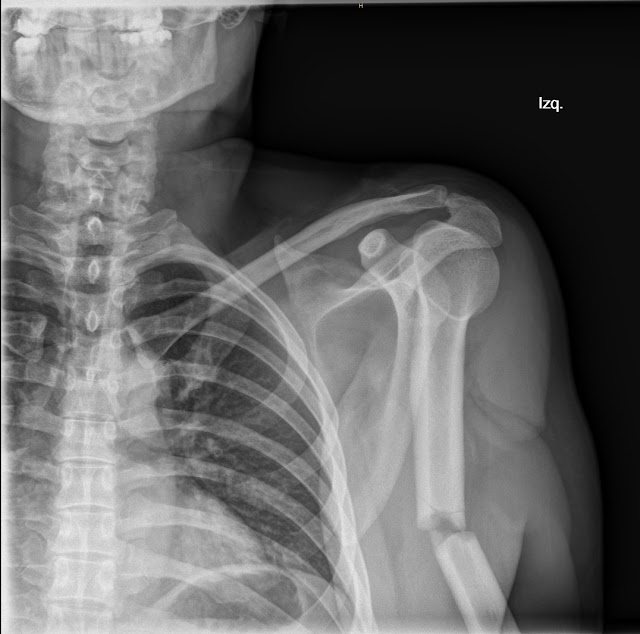

Fractura del tercio medio humeral

Las fracturas de la diáfisis humeral representan entre el 1,2 y 1,5% de todas las fracturas de las extremidades en los adultos y el 3-5% de todas las fracturas esqueléticas. No son raras en los servicios de urgencias hospitalarias, pero tampoco es que sean extremadamente frecuentes.

Hace tiempo, concretamente el 10 de Marzo de este año, escribía una entrada en el blog en la que hablaba de las fracturas de la diáfisis humeral, a propósito de un caso que había atendido hacía unos días. Entre otras cosas explicaba entonces que definimos a estas fracturas como aquellas que se producen entre el borde inferior del pectoral mayor, por arriba, y una línea convencional que pasa a 4 traveses de dedo por encima de la interlínea articular del codo. Hablé de su epidemiología, del mecanismo de fractura, y de sus clasificaciones, por lo que en esta ocasión no voy a hacerlo y remito al que quiera refrescar la memoria a la entrada de ese día.

En aquella ocasión mostré las radiografías de una aparatosa fractura del tercio superior de la diáfisis humeral de un paciente.

Hoy voy a mostrar las imágenes que tenía guardadas de otro caso que vi hace tiempo de una fractura de tercio medio de diáfisis humeral.

Este tipo de fracturas de la diáfisis del húmero que son distales a la inserción del deltoides, pueden dar lugar a abducción del fragmento superior y desplazamiento proximal del fragmento distal por la contracción muscular sin oposición. Son por lo tanto fracturas con desplazamiento. Sin embargo en este caso, no se presentaba.

Estamos ante una fractura TipoA1 de la clasificación AO